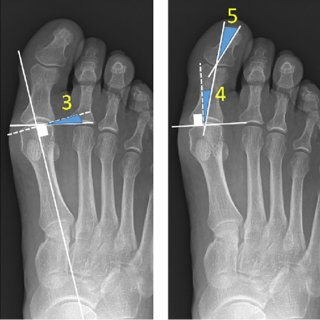

Deformările degetelor cauzate de hallux valgus sunt clasificate pe trei stadii – ușoare, moderate și severe, – până în punctul în care devin progresiv fixe, cu pierderea mobilității articulațiilor interfalangiene. Examinarea monturilor se realizează prin examen radiologic, pentru calcularea gradului exact de deviere a halucelui față de metatarsianul I.